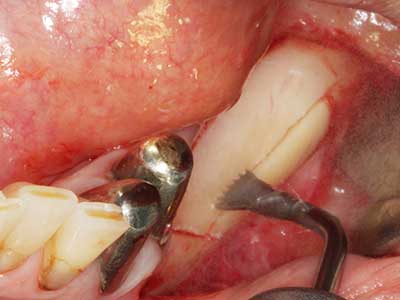

Fig. 20: The removed bone cover is re-adapted and fixed with an osteosynthesis screw (KLS Martin, Tuttlingen).